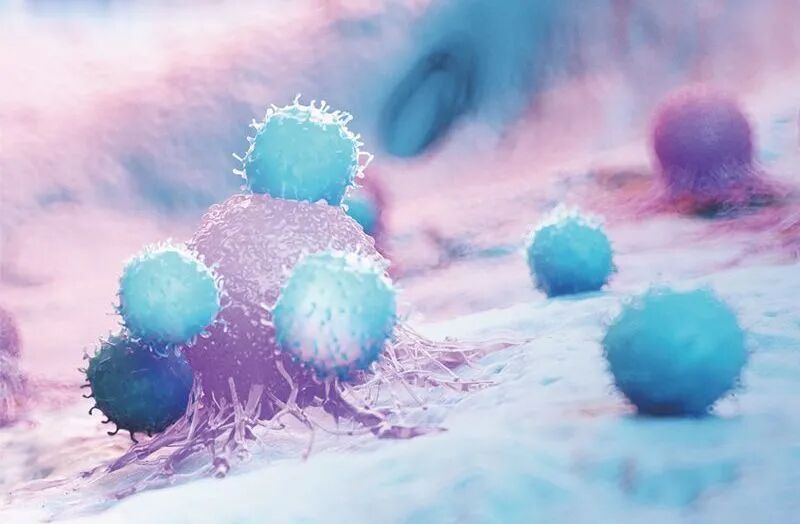

面对慢性炎症的威胁,我们并非束手无策。事实上,我们的身体内就有一套精密的消炎机制——免疫细胞。它们不仅能够对抗感染,还能从源头消除炎症,维持机体内环境的稳定。

巨噬细胞:是炎症反应的关键调节者。它们既能释放促炎因子启动炎症反应,也能分泌抗炎物质促进炎症消退。

调节性T细胞:是免疫系统的“和平使者”,它们通过抑制过度活跃的免疫反应来防止炎症失控。这些细胞能够分泌抗炎因子,抑制其他免疫细胞的活性,从而维持免疫耐受和防止自身免疫病的发生。

间充质干细胞:它也具有强大的抗炎和免疫调节功能。它们能够感知炎症环境,并迁移到受损部位,通过直接接触和分泌可溶性因子的方式,抑制过度炎症反应,促进组织修复和再生。

自然杀伤细胞、树突状细胞:它们也都在炎症调节中扮演着重要角色,它们共同构成一个精细的免疫调节网络,维持着炎症与抗炎症的平衡。